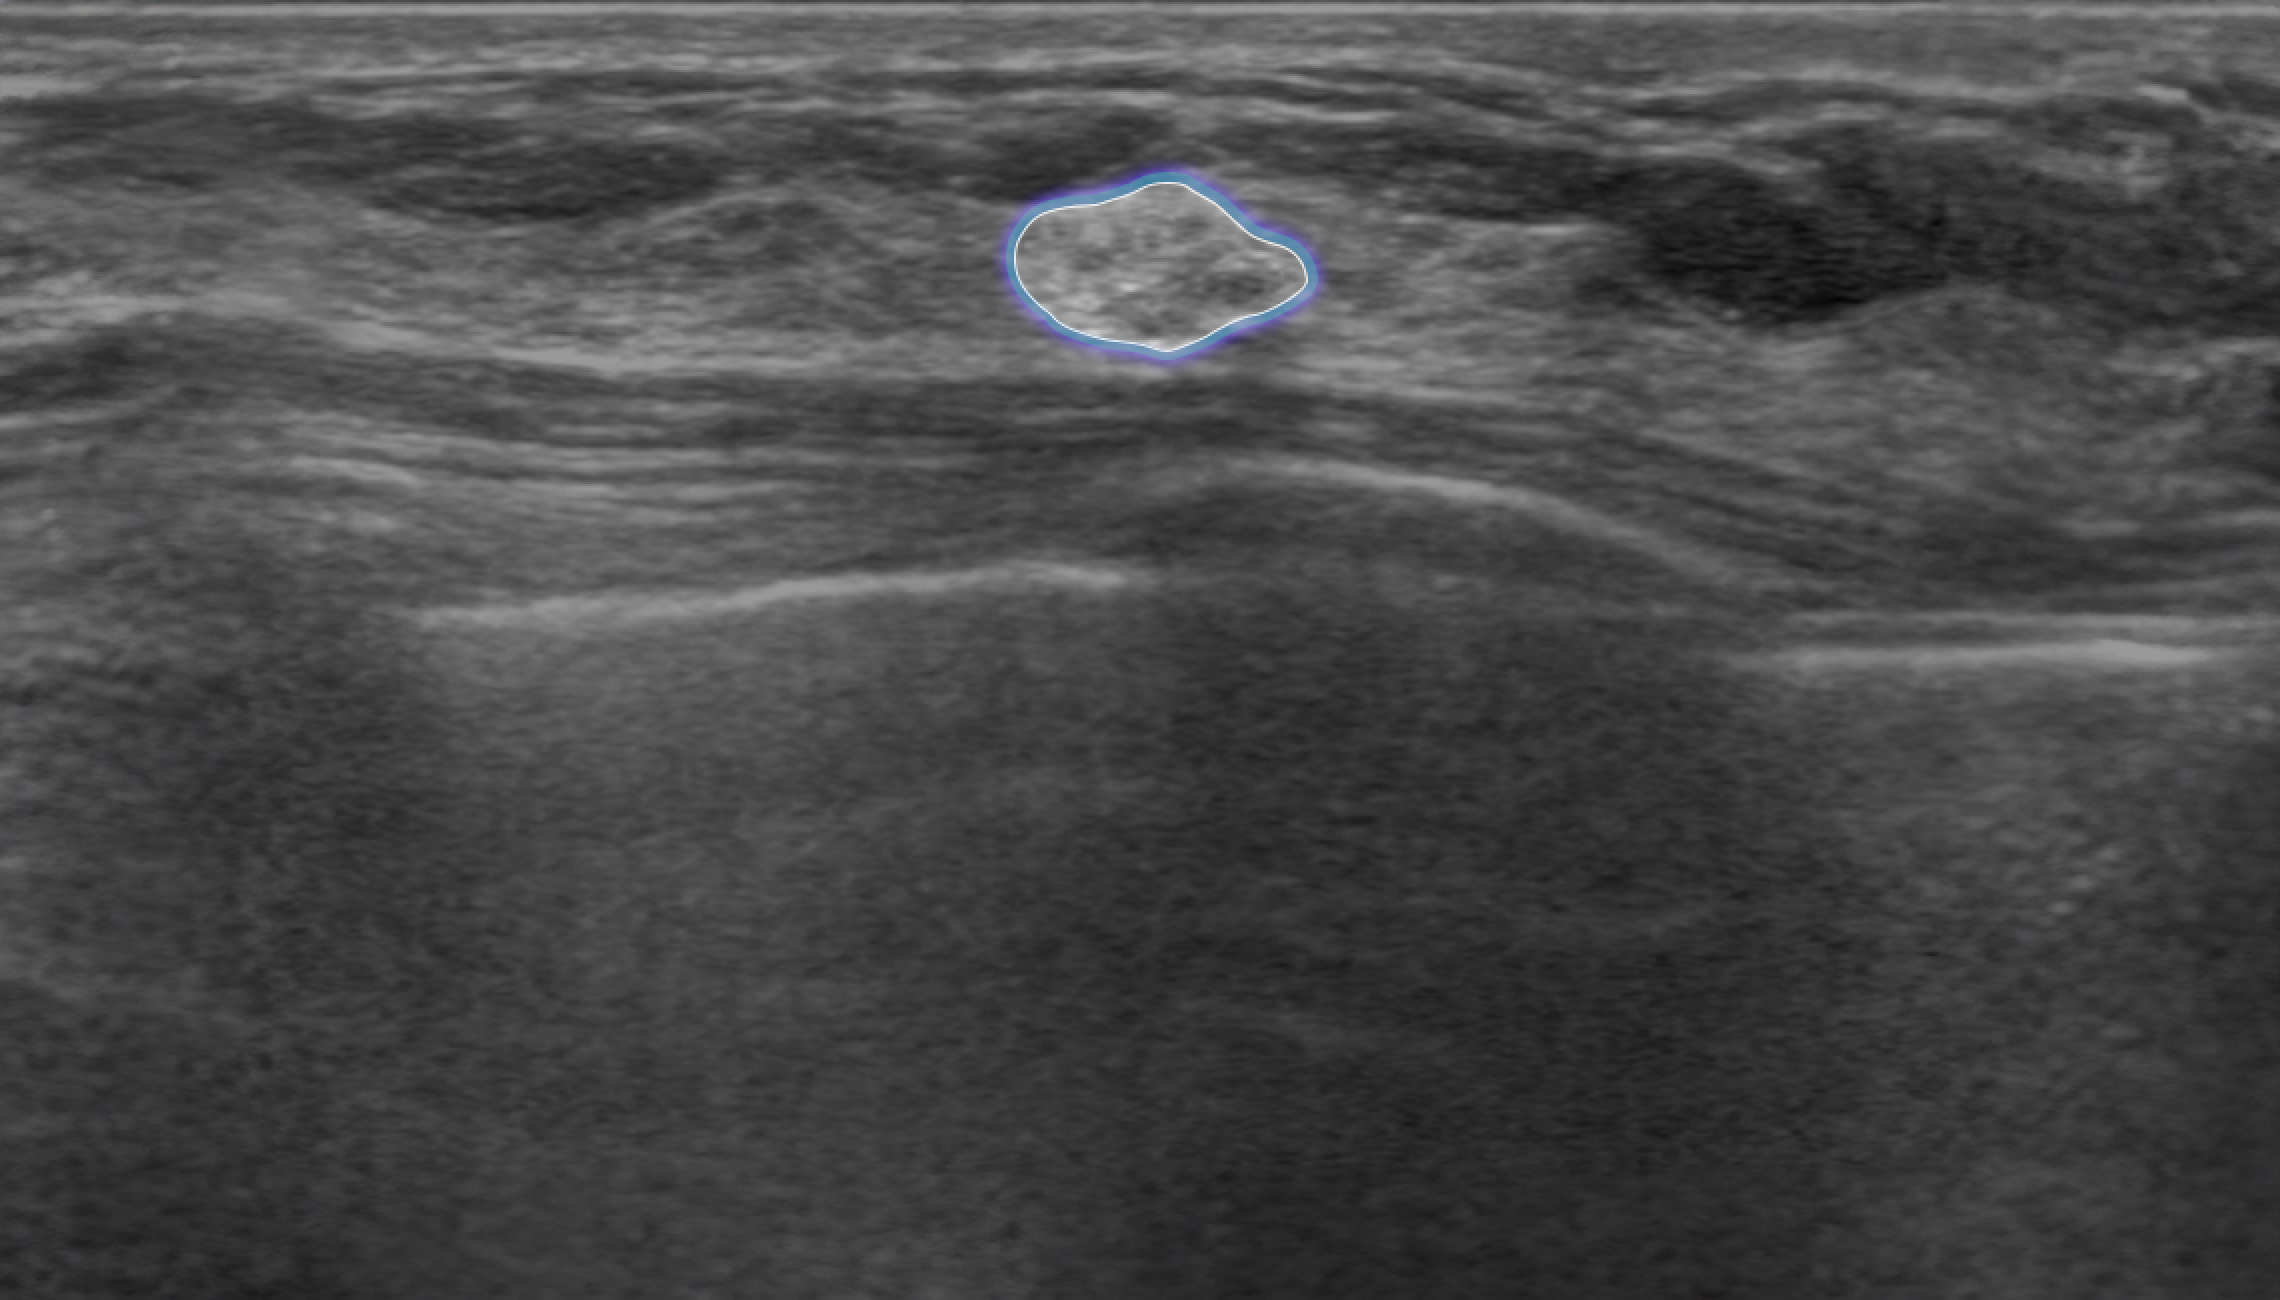

Automatic Detection of Abnormal Lesions

Automatically detects the locations of abnormal lesions in breast ultrasound images in real time.